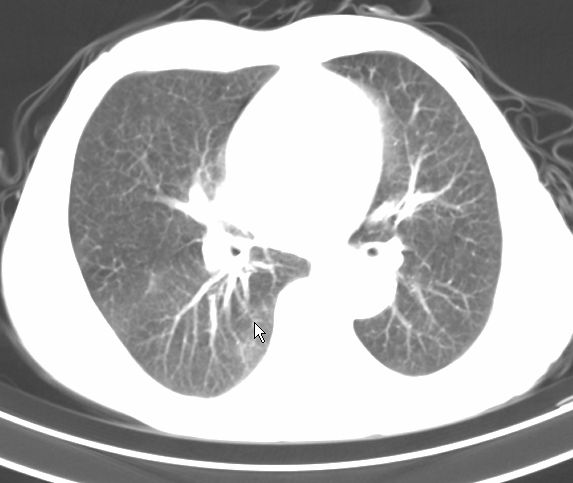

标题: CT17095:胸部病变请大家看看是什么性质的

请大家看看是什么性质的。炎性病变首先考虑哪一种炎症。

支持右肺上叶前段\\下叶内基底段感染,建议抗炎治疗后复查,除外结核.

支持右肺上叶前段\\下叶上段感染,建议抗炎治疗后复查,除外结核.

支持右肺上叶前段、下叶内基底段感染,建议抗炎治疗后复查,除外结核.

右肺上叶前段及下叶内基底段感染性病变;建议抗炎治疗后复查。

楼主说是炎症,凭啥?典型的周围型肺癌(腺癌可能性大),肝内可能已有转移,强化看看吧。